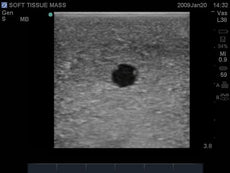

Brand New! 2nd Generation upper torso ultrasound guided central line placement training model with transparent tissue insert allows users to develop and practice the skills necessary to gain proficiency in using ultrasound to guide central catheter insertions in the internal jugular vein (IJ), subclavian vein, and axillary vein while revealing the venous and arterial vessels as well as accessory boney structures. Developed with the goal of helping clinicians bridge the learning gap by allowing them to see the internal anatomical structures with their eyes as well as with ultrasound imaging, our transparent central line placement tissue offers superb ultrasound hands-on training. Using Blue Phantom proprietary simulated human tissue, this very realistic and ultra-durable transparent central venous access ultrasound training model is excellent for training clinicians in the psychomotor skills associated with ultrasound guided central line placement procedures. These ultrasound imaging skills include; using ultrasound system controls, transducer positioning and movement, recognition of arterial and venous anatomy, using ultrasound to target the appropriate vessels for cannulation, and performing a central venous access procedure.Helps

- Superb ultrasound imaging characteristics

- Tissues match the acoustic characteristics of real human tissue so when you use your ultrasound system on our training models, you experience the same quality you expect from imaging patients in a clinical environment

- Tissues match the acoustic characteristics of real human tissue so when you use your ultrasound system on our training models, you experience the same quality you expect from imaging patients in a clinical environment